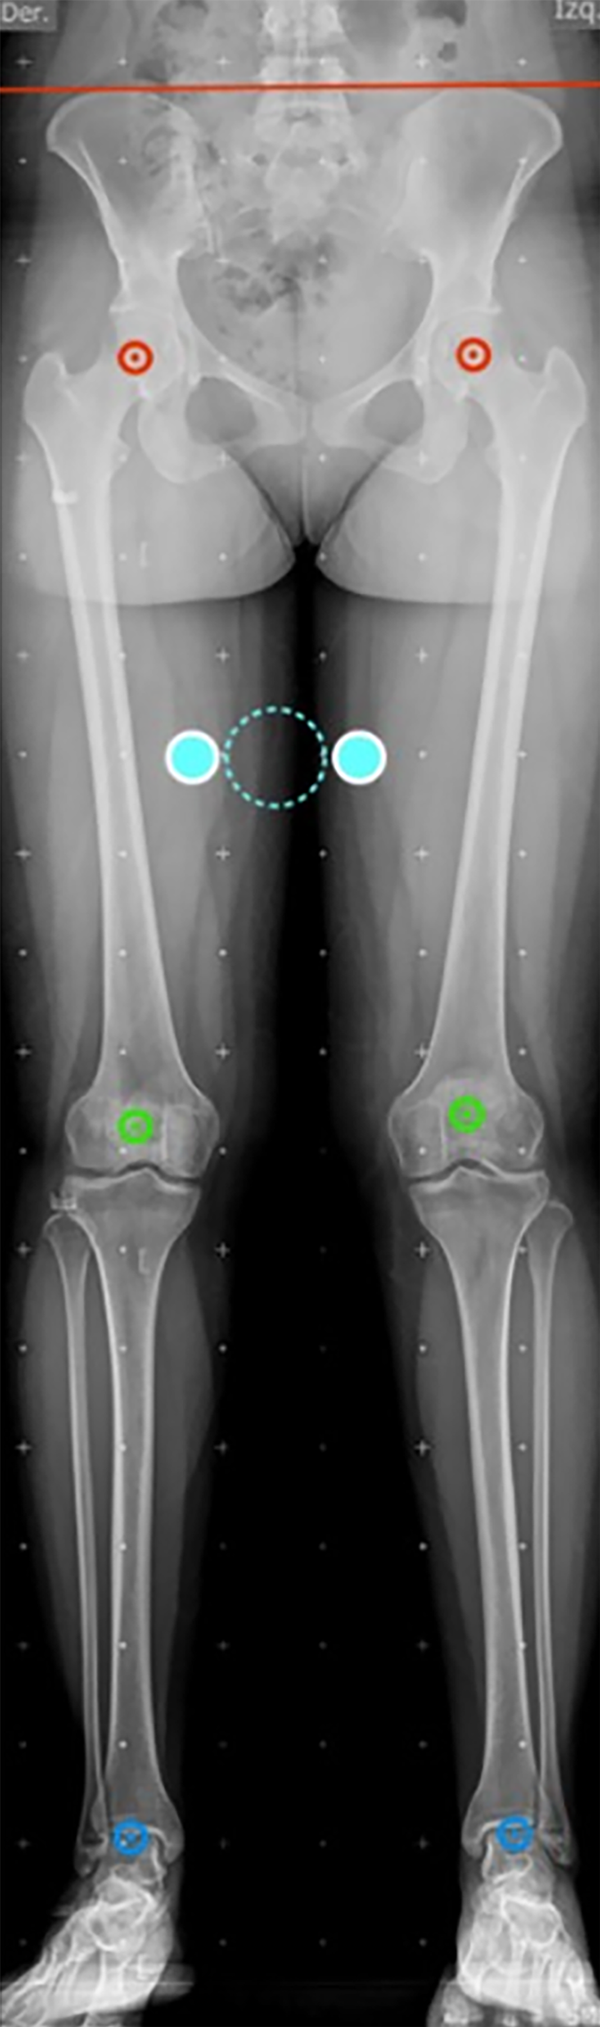

Según Paley,18 la imagen adecuada debe permitir la visualización de la cadera, rodilla y tobillo, con la rótula centrada en los cóndilos femorales, sin embargo, cuando hay un valgo severo, esta referencia se pierde y se debe tomar el eje de flexoextensión de la rodilla. Adicionalmente, la discrepancia de longitud se debe corregir, y la rotación máxima permitida para no alterar los valores es de 5° (figs. 1 y 2).

Figura 1: Radiografía panorámica adecuada con los parámetros de Paley para realizar un test de mal alineamiento: la línea roja evidencia la adecuada altura de las alas ilíacas, se observan las tres articulaciones; el círculo verde señala el centro de las rótulas posicionadas entres los cóndilos y el círculo punteado azul señala las guías de calibración a 5 cm, punto importante para las mediciones.